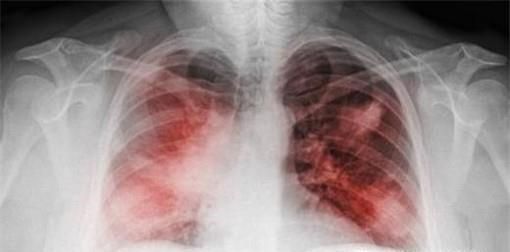

肺炎是目前世界上比较严重的疾病,那么大家知道肺炎的症状有哪些呢?接下来这篇指南将告诉你答案。